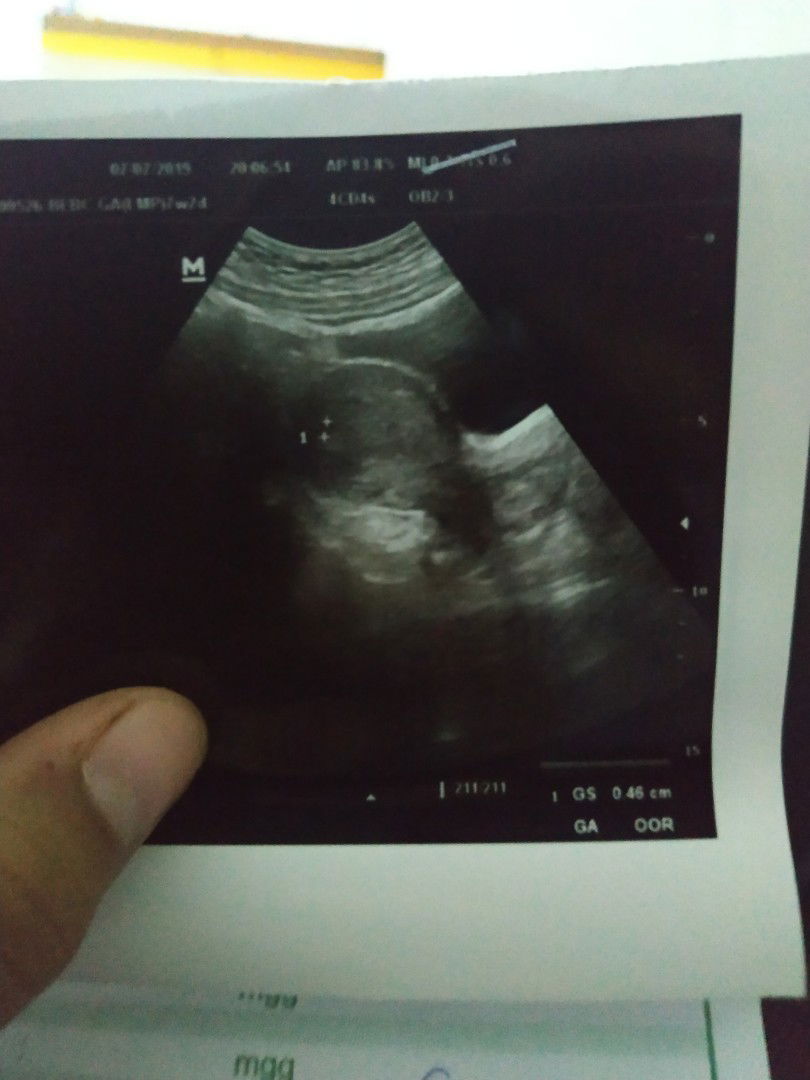

janin belum terlihat

Bun.. sharing dong usia 7 minggu d usg belum kelihatan dede nya.. Ada yg mengalami hal yg sama? Kata bidan d suruh dtg lagi 2 minggu lagi.. Menurut bunda waktu yang tepat untuk usg itu kapan ya bun??